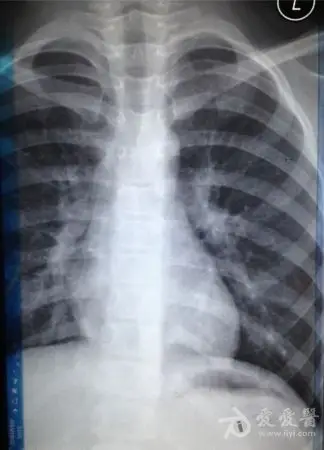

新生儿30天得肺炎,现在在妇幼icu,这是胸片,很严重吗

胸片可见两肺弥漫炎性渗出影,因此诊断为小儿支气管肺炎

请各位大夫帮看看,孩子这个胸片正常了吗?还需要继续吃药吗?